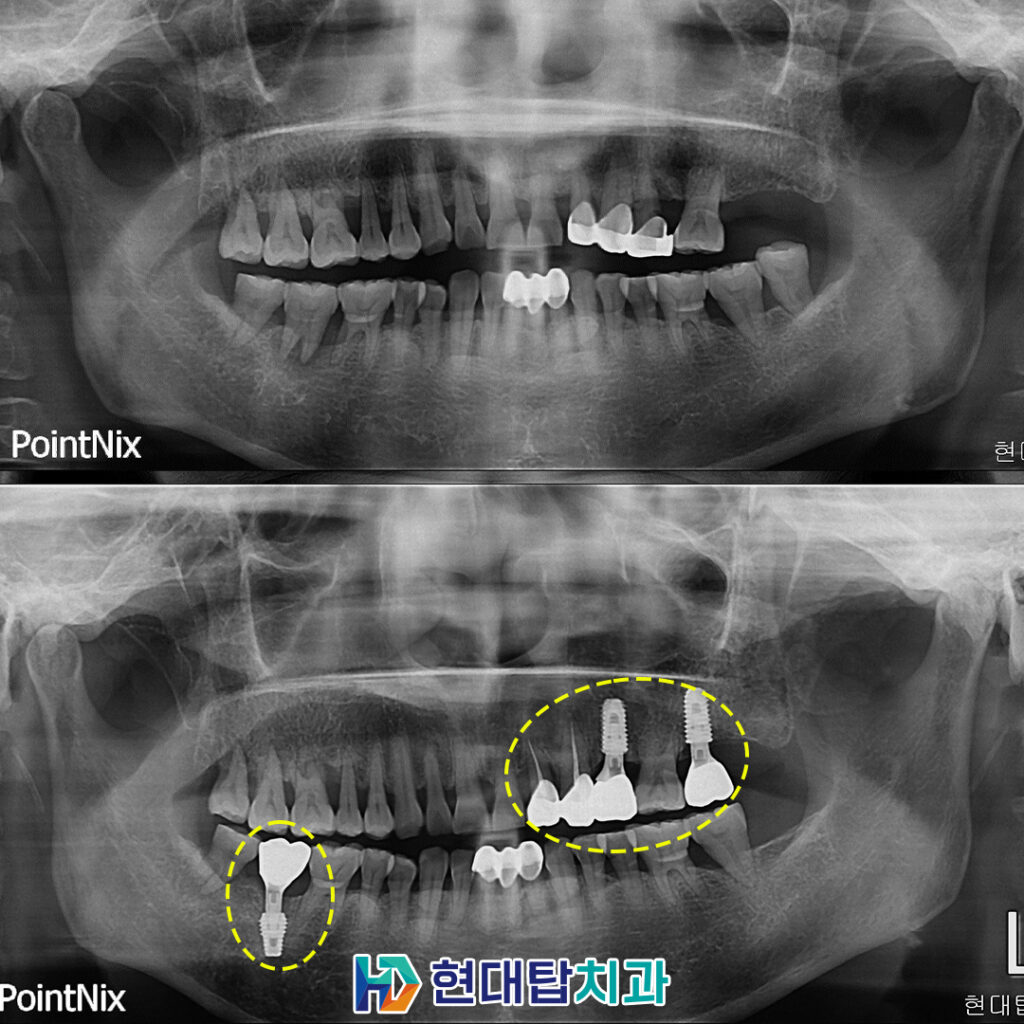

위 환자분께서는 식사하실 때 이가 흔들리는 느낌이 드신다며 치료를 받으러 내원해 주셨는데요. 파노라마 촬영 결과, 왼쪽 위와 오른쪽 아래 어금니 부위에 치아 뿌리 염증으로 잇몸뼈가 많이 녹아 치아가 흔들리는 것으로 판단되어 예후가 좋지 않은 치아를 발치한 후 임플란트 계획을 수립하였습니다.

임플란트의 최종 보철물까지 완료한 모습입니다. 임플란트는 잇몸뼈와 융합이 가장 중요하기 때문에 식립 후 잇몸뼈와 인공치근이 단단하게 굳을 수 있는 기간을 기다려준 후 최종 보철물을 제작하여 보다 튼튼하고 안정적인 사용이 가능합니다. 환자분께서도 걱정 없이 편안한 식사에 만족도가 매우 높으셨습니다.